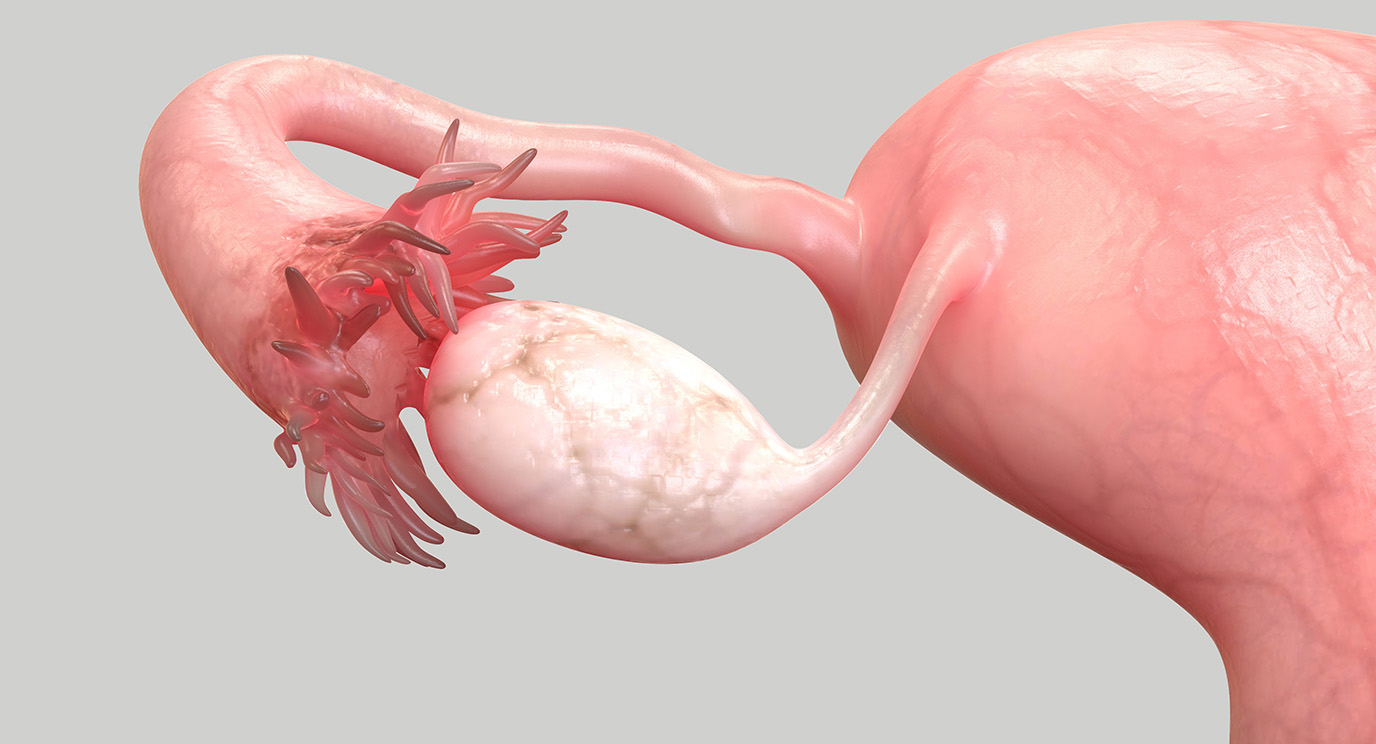

Real Fallopian Tube

Real Fallopian Tube